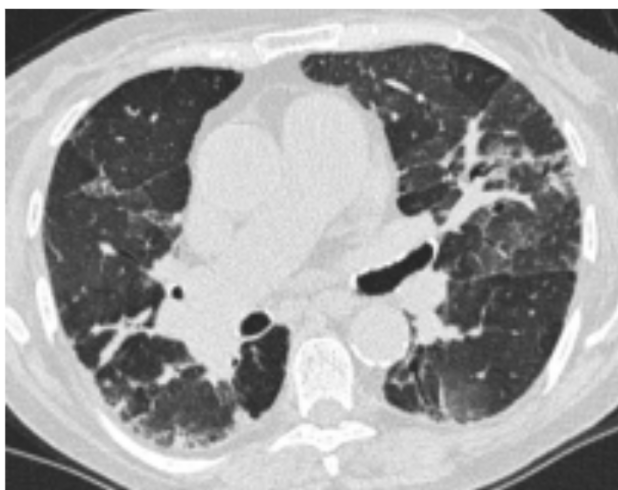

Fibrotisk AA

HRCT ved Fibrotisk AA inddeles ligeledes i ”ty pisk”, ”forenelig med” eller ”ubestemt” for fibro tisk AA. Ved den typiske fibrotiske AA ses retiku lering, traktionsbronkiektasier og evt. bikageteg ning i de mellemste og basale lungeafsnit. Sam tidig ses tegn på small airways disease med

centrilobulære noduli, mosaikattenuering og air trapping (figur 2). Fund af ”three-density-sign”, dvs. samtidig forekomst af matglastegning (øget attenuation), normalt lungevæv (normal attenua

tion) og mosaikattenuering (nedsat attenuation) er patognomonisk for fibrotisk AA. Tilstedevæ relse af fibrose er forbundet med en dårligere prognose.

Figur 2. HRCT ved fibrotisk allergisk alveolitis.